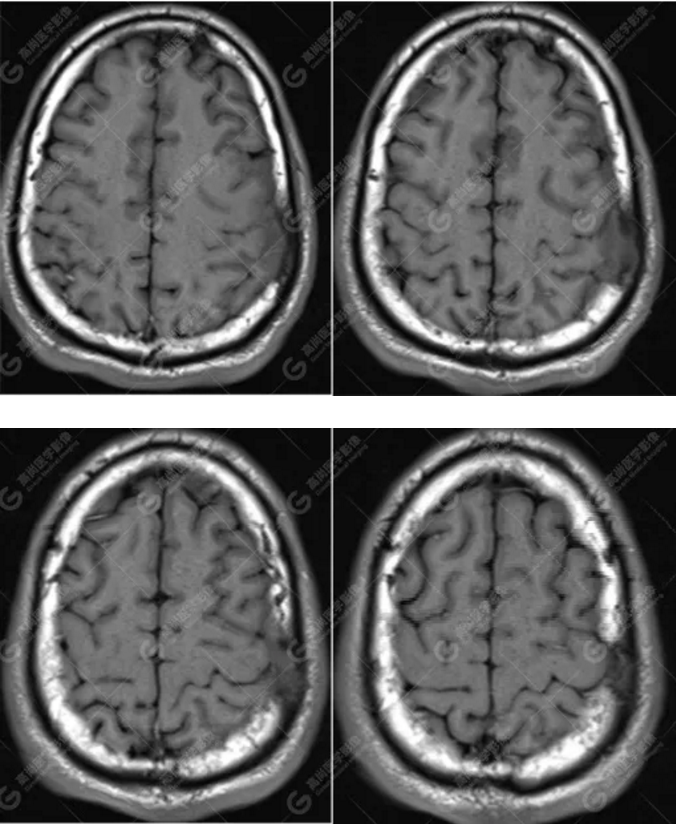

MR圖像

左側額頂部顱骨骨質破壞并相鄰硬腦膜增厚強化,考慮Rosai Dorfman?。≧DD)可能,需與朗格漢斯細胞組織細胞增生癥鑒別。

總之,顱內RDD是一種罕見的硬腦膜良性病變,若 MRI發(fā)現(xiàn)顱內基于硬腦膜扁平或匍匐生長的孤立或者多發(fā)腫塊,CT 檢查未見鈣化,而MR檢查T2WI及 DWI呈低信號,增強明顯均勻強化,應考慮到 RDD 的可能。